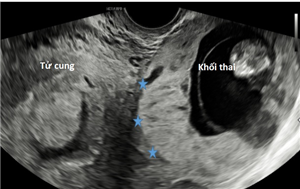

Thai lạc chỗ ở gan (TOG) là một thể không thường gặp của thai trong ổ bụng (TTOB)